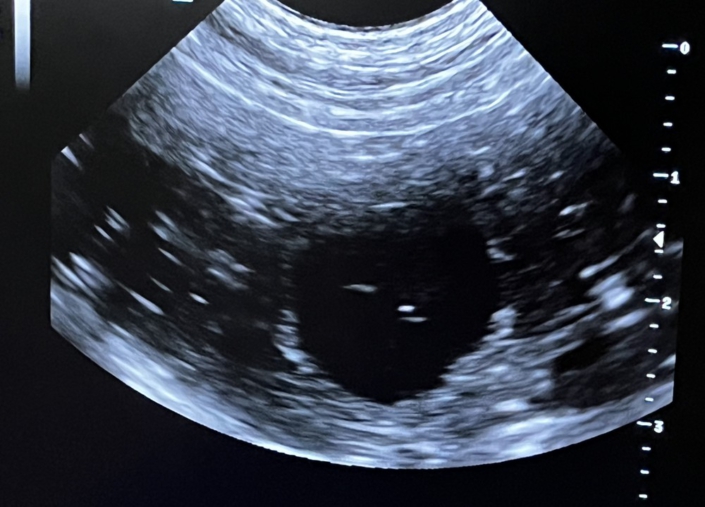

Poppy ist tragend !!!

Schöne Bildchen hat der Ultraschall gestern hergegeben. Poppy ist jetzt an ihrem 24/25. Tag der Trächtigkeit und trägt schön gleichmäßig verteilt, kleine sich entwickelnde Früchtchen. Ihr selbst geht es gut, na ja, man muss halt mehr kuscheln und die Spaziergänge sind ruhiger angelegt.